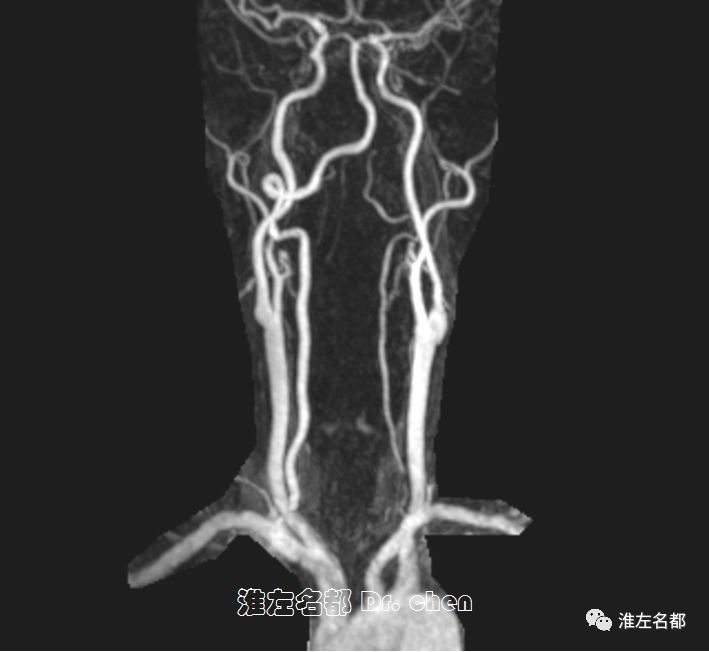

△3D-TOF-MRA:左侧椎动脉细小,其末端未见显影。